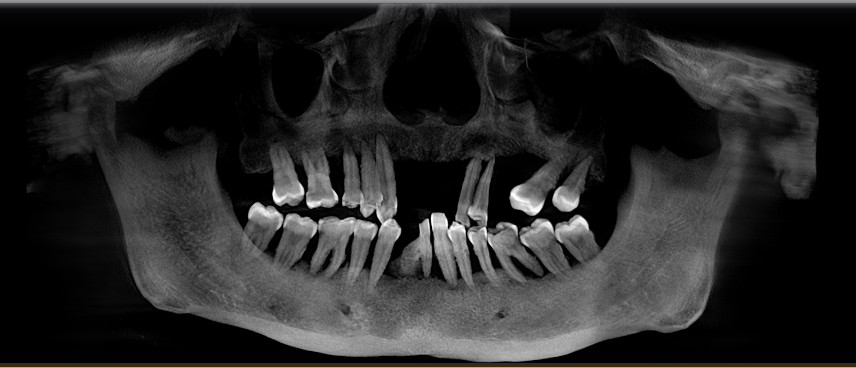

患者女,五十岁,近几年出现刷牙出血和牙齿的松动,甚至部分脱落,近期前来我院就诊。患者全身健康,否认糖尿病,否认家族病史。临床检查:口腔卫生差,可见大量菌斑,软垢。牙石+++,牙龈暗红。根面暴露,前牙部分脱落。X线示牙槽骨吸收至根尖1/3。

治疗计划:1拔除无法保留的牙齿。2牙槽骨吸收至根尖2/3以上的患牙进行根管治疗。3分次进行牙周刮治。4缺失牙修复。5定期维护